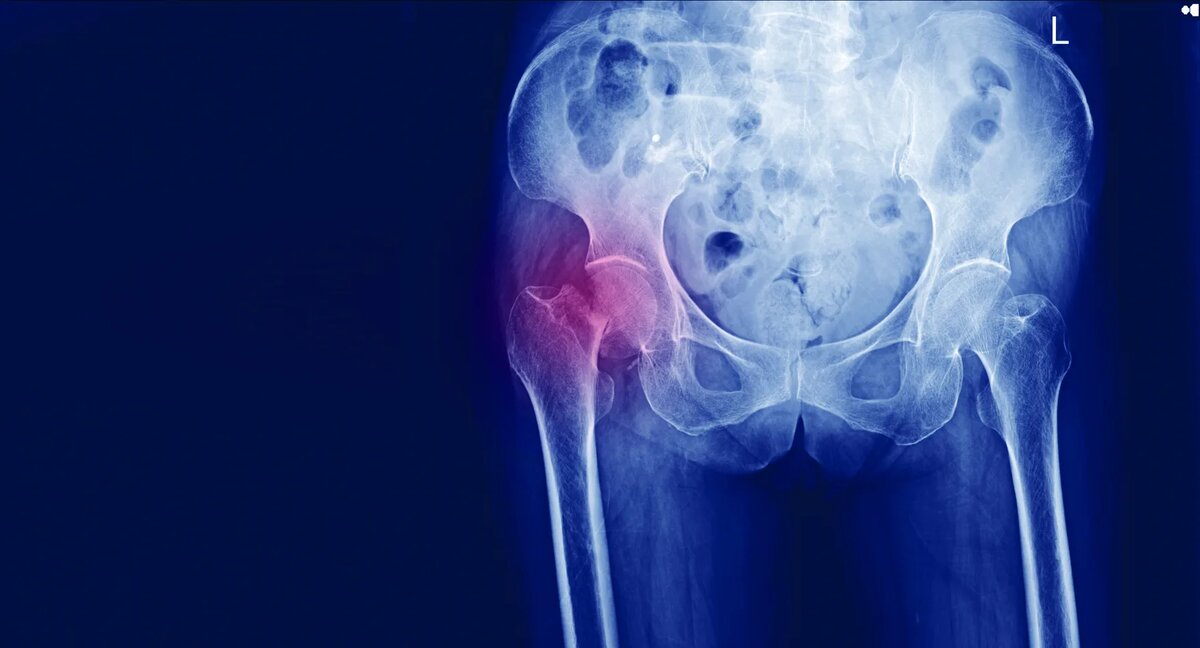

Перелом шейки бедра: не просто травма, а билет в лежачую жизнь. Что делать, чтобы выжить и снова ходить.

Что такое шейка бедра? Это не шея в привычном понимании. Это тонкая, хрупкая часть бедренной кости, которая соединяет ее головку (ту, что входит в тазобедренный сустав) с основным телом кости. Сломать ее молодому человеку нужно постараться – ДТП, падение с высоты. Пожилому человеку, особенно женщине с остеопорозом (разрежением костной ткани), иногда достаточно оступиться на ровном месте, поскользнуться, резко повернуться. Хруст – и все. Кость, которая держит на себе вес всего тела, теряет опору.